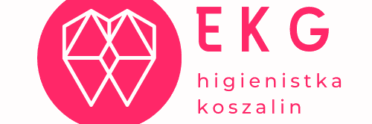

Wybielanie zębów – efekt przed i po zabiegu

Zęby po wybielaniu, rozjaśnione o 2 tony.